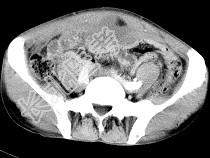

- 单项选择题男,56岁, 无规律上腹痛,左锁骨上淋巴结肿大, 消瘦、乏力,影像检查如图, 最可能诊断为 ( )

A、胃及腹腔淋巴瘤

B、胃癌并盆腔种植

C、胃溃疡穿孔

D、肠系膜淋巴管瘤

E、腹膜结核